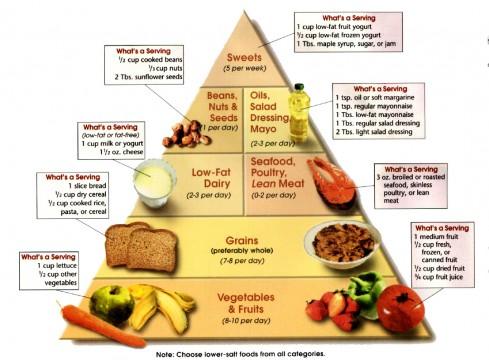

1997年4月17日

发现饮食疗法可以干预高血压。将患者分为(1)典型的美国饮食,(2)低糖且水果蔬菜丰富的食物和(3)联合水果蔬菜丰富且低脂少肉的饮食。后两种饮食方式均可以降低血压,这就是DASH饮食的来源。如今,DASH饮食和运动一起,已经成为了抵抗高血压的一线治疗方式。